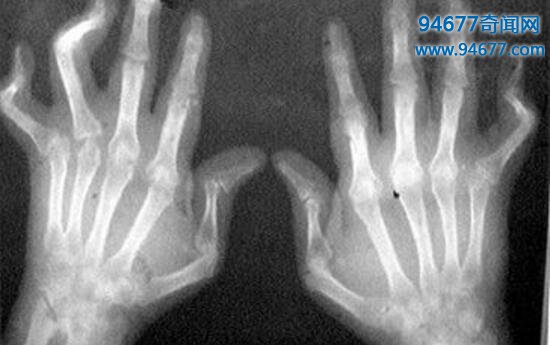

五、类风湿关节炎

目前来说,对于类风湿关节炎的病因还没有明确,可能跟内分泌、职业、代谢、病毒感染和遗传有关,是一种属于自身免疫炎性病症,该病多发在手、腕和足等小关节,且会反复发作,早期会出现关节红肿和出出行动不便,晚期的关节会出现僵硬畸形,有时伴有骨和骨骼的萎缩,甚至会致残,还会蔓延至全身病变,患者会有发热、疲乏无力、周围神经病变等现象。